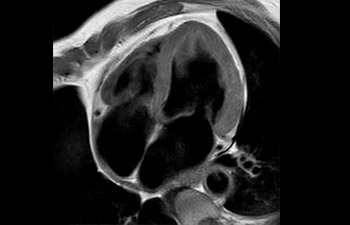

• Es una innovadora técnica de aceleración que no solo permite agilizar las secuencias, sino todo el estudio. • Implementación especial con la que las exploraciones en 2D y 3D pueden llegar a ser hasta un 50% más rápidas con una calidad de imagen prácticamente equivalente.1

• Se puede usar con todos los contrastes y con todas las regiones anatomías.